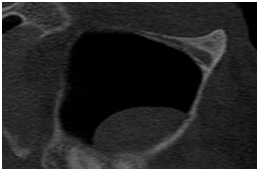

• Auxiliar no diagnóstico e delimitação das lesões patológicas

Avaliação de patologias Avaliação de patologias